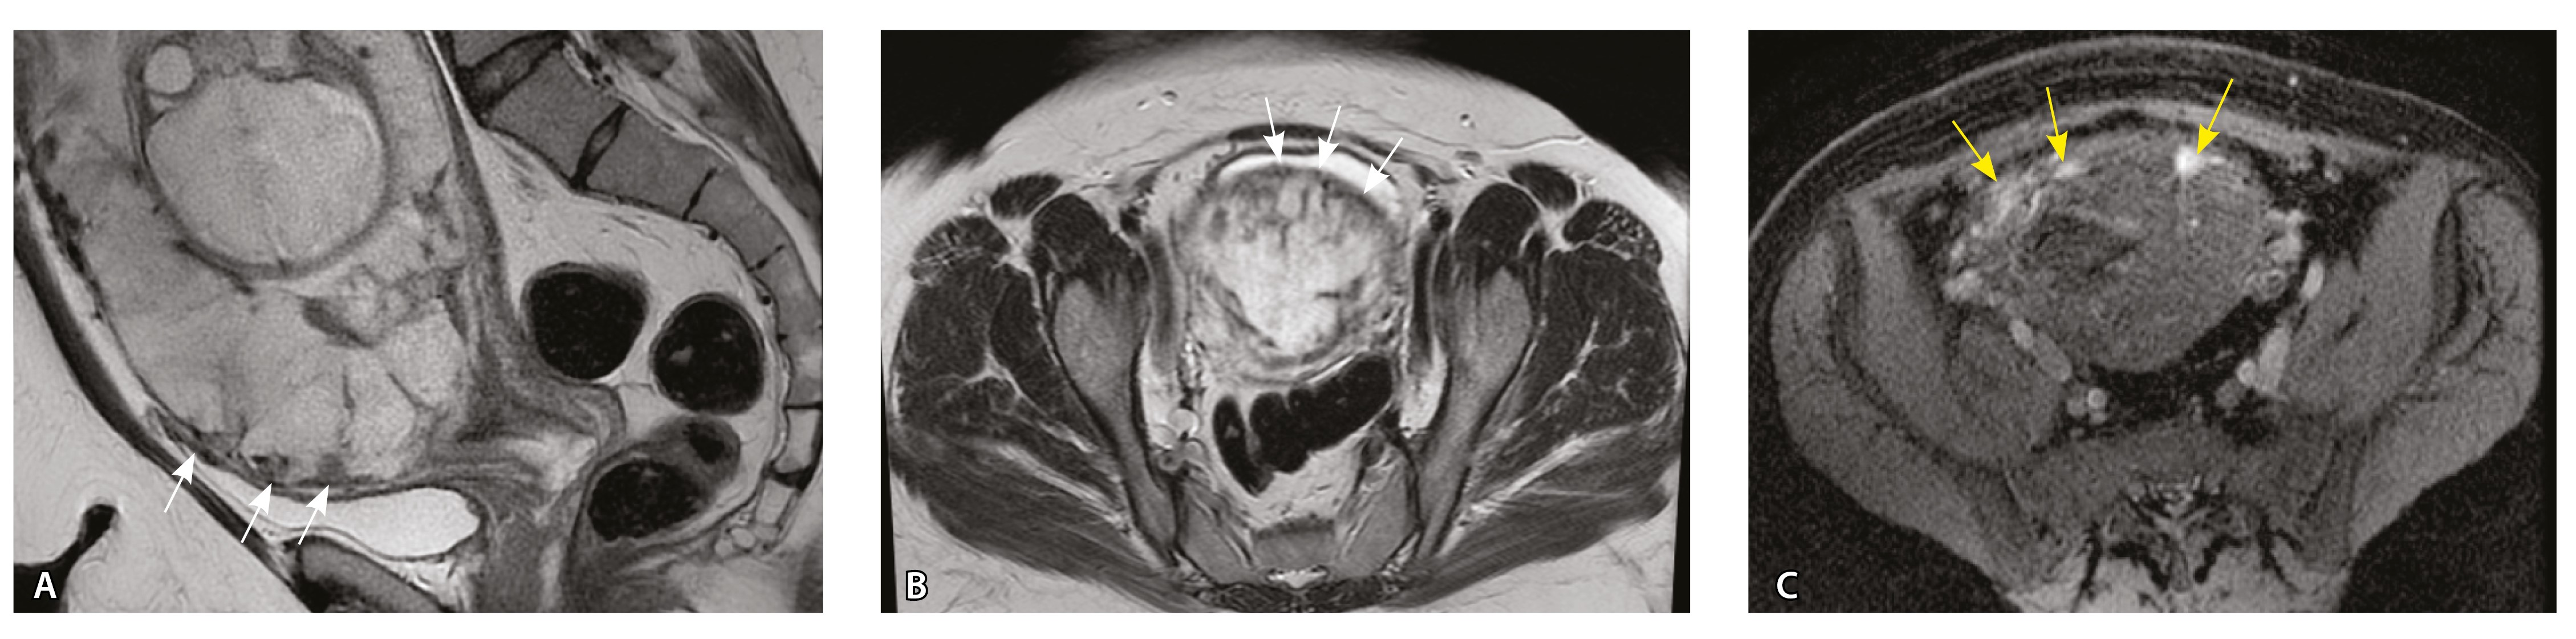

Сосуды 2-го типа. Единичные сливающиеся сосудистые полости в маточно-плацентарной области, мелкие ретроплацентарные гематомы, участки с белковым содержимым по МР-сигналу в зоне контакта ворсин со стенкой матки (рис. 4).

Рис. 4. Беременность 32 недели, pl. accreta, PAS 1 по FIGO. На магнитно-резонансных томограммах в режиме Т2-взвешенного изображения в сагиттальной (А) и аксиальной (Б) плоскостях видны сосуды на границе маточно-плацентарной области, сливающиеся между собой (белые стрелки), без выраженного дефицита толщины миометрия и рубца от кесарева сечения, без признаков выбухания стенки матки. На Т1-взвешенном изображении в режиме подавления сигнала от жировой ткани в аксиальной плоскости (В) выявляется наличие участков повышенного сигнала (желтые стрелки) на границе маточно-плацентарной области, что соответствует геморрагическому компоненту в подострой/хронической стадии (ретроплацентарные гематомы) либо белковому содержимому (фибриноид)

Непосредственное сравнение МР-картины с операционным материалом подтвердило, что полости с геморрагическим компонентом соответствовали ретрохориальным гематомам различной давности, чаще подострой и хронической стадий, которые состояли из гемолизированных эритроцитов, нитей фибрина сетчатого строения, а также замурованных атрофичных ворсин (рис. 5). Следовательно, констатация на МРТ фиксированных геморрагических полостей в маточно-плацентарной области отражает не гиперваскуляризацию стенки матки, а наличие ретрохориальных гематом в подострой/хронической стадии, что следует учитывать в клинической практике.

Рис. 5. Сосуды 2-го типа при гиперваскуляризации стенки матки при патологической инвазии: А – организованная ретрохориальная гематома в маточно-плацентарной области, в ее составе много инволютивных якорных ворсин (окраска по Маллори; × 100); Б – в составе гематомы видна пролиферация цитотрофобласта (иммуногистохимическое исследование, маркер цитокератин 8; × 100)

Как видно на рис. 6, сосуды 2-го типа не встречались в норме и при плотном прикреплении плаценты (gr 2), с одинаковой частотой наблюдались при pl. accreta (gr 3) и pl. increta (gr 4) и были обнаружены у 94,4% пациенток с pl. percreta (gr 5) (р < 0,001, хи-квадрат Пирсона).

Сосуды 2-го типа не встречались в норме и при плотном прикреплении плаценты, что говорит об их специфичности для приращения плаценты. Данные сосуды выявлялись при pl. accreta (52,9%), pl. increta (50%) и pl. percreta (94,4%). Они представляли собой сливающиеся сосудистые полости в маточно-плацентарной области, мелкие ретрохориальные (ретроплацентарные) гематомы, участки с белковым содержимым, что, по данным патоморфологического исследования, может соответствовать увеличению количества плодного фибриноида. Считается, что именно фибриноид служит дополнительным фактором, способствующим инвазии трофобласта и активному ангиогенезу в стенке матки [16]. Учитывая, что данный тип сосудов встречался чаще остальных вариантов сосудов в группе пациенток с pl. accretа, полагаем, что он является патогномоничным для данной глубины врастания плаценты. В то же время при глубокой инвазии по типу pl. increta и pl. percreta характерно сочетание данного типа сосудов с сосудами, описанными ниже.